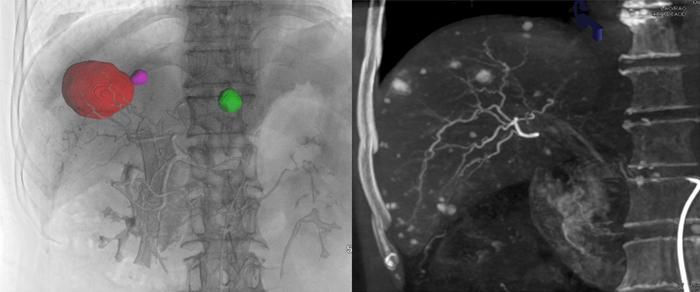

Cone-beam computed tomography stands out as a promising alternative due to its unique volumetric imaging capabilities. CBCT employs a cone-shaped X-ray beam to produce three-dimensional reconstructions of anatomical structures with a level of detail that traditional modalities may not achieve. This enhanced visualization facilitates automatic detection and navigation of targeted vessels, offers real-time fluoroscopic guidance, and enables precise post-TACE assessment of embolization. Recognizing the advantages of CBCT, interventional radiologists are drawn to it as a potential solution to the limitations faced with traditional imaging methods. Despite its advantages, full clinical integration of CBCT continues to be stymied by obstacles such as insufficient awareness among practitioners and a lack of consistency in operational parameters and application protocols.

Despite the significant role that cone-beam computed tomography (CBCT) plays in interventional therapies for liver malignancies, it remains an underutilized imaging modality in clinical practice. Various complicating factors hinder its full integration, including nonstandardized operational protocols and limited recognition among interventional radiologists. Such obstacles have prompted the Chinese College of Interventionalists to issue a comprehensive consensus statement, aimed at standardizing and advancing the application of CBCT within interventional liver treatments. This significant document details CBCT scanning techniques, operational standards, and the modality’s potential clinical applications, ensuring a uniform approach to its use.

To tackle these challenges, the consensus statement published by the Chinese College of Interventionalists serves as a guideline for standardizing the usage of CBCT in liver malignancy treatments. Registration on the International Practice Guidelines Registration and Transparency Platform indicates the document’s credibility and adherence to evidence-based practices. The consensus delineates essential CBCT scanning techniques and operational standards while illuminating the modality’s clinical applications across a variety of interventional procedures. Furthermore, it provides explicit recommendations to address existing challenges, such as limited soft tissue contrast, potential radiation exposure, image artifacts, resolution constraints, and restricted fields of view.